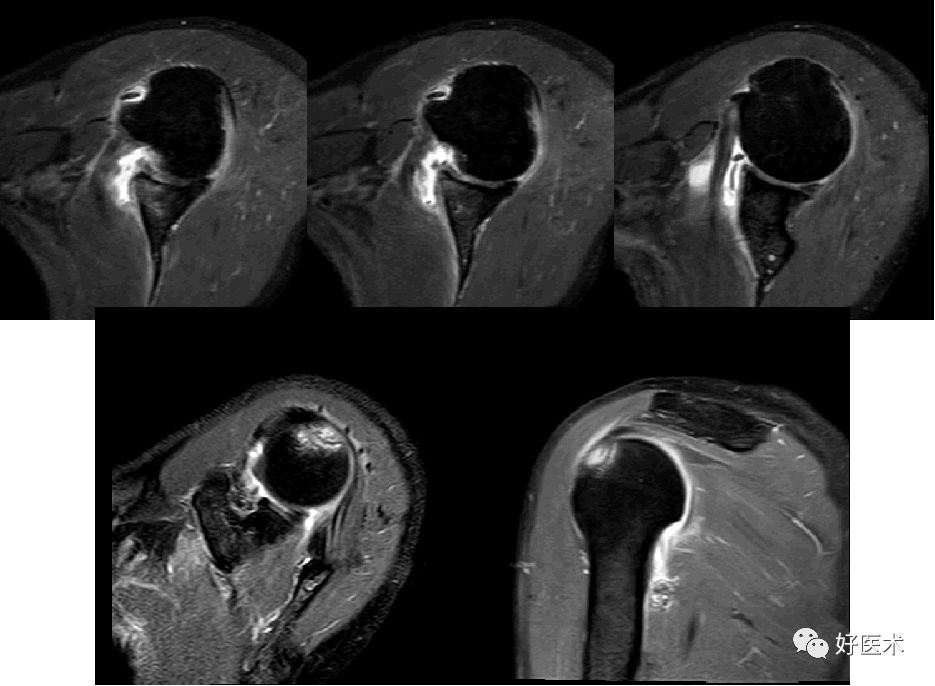

Bankart损伤的MR表现

-

三角形变钝

盂唇撕裂:关节盂唇软骨与盂缘可见线状高信号影并连续到关节面下

盂唇完全消失或盂唇明显移位

若盂唇损伤合并关节盂骨质损伤,称为骨性Bankart病变

骨性Bankart病变

MR间接关节造影1.5T轴位T1W脂肪抑制(TR=460s,TE=90s)

SLAP、Bankart合并Hill-Sach损伤